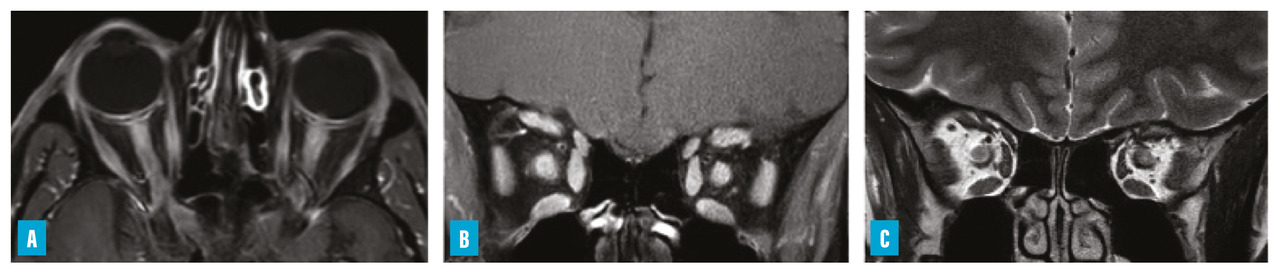

– névrite optique rétrobulbaire (NORB) sévère, volontiers étendue, parfois bilatérale, pouvant toucher le chiasma (fig. 1) ;